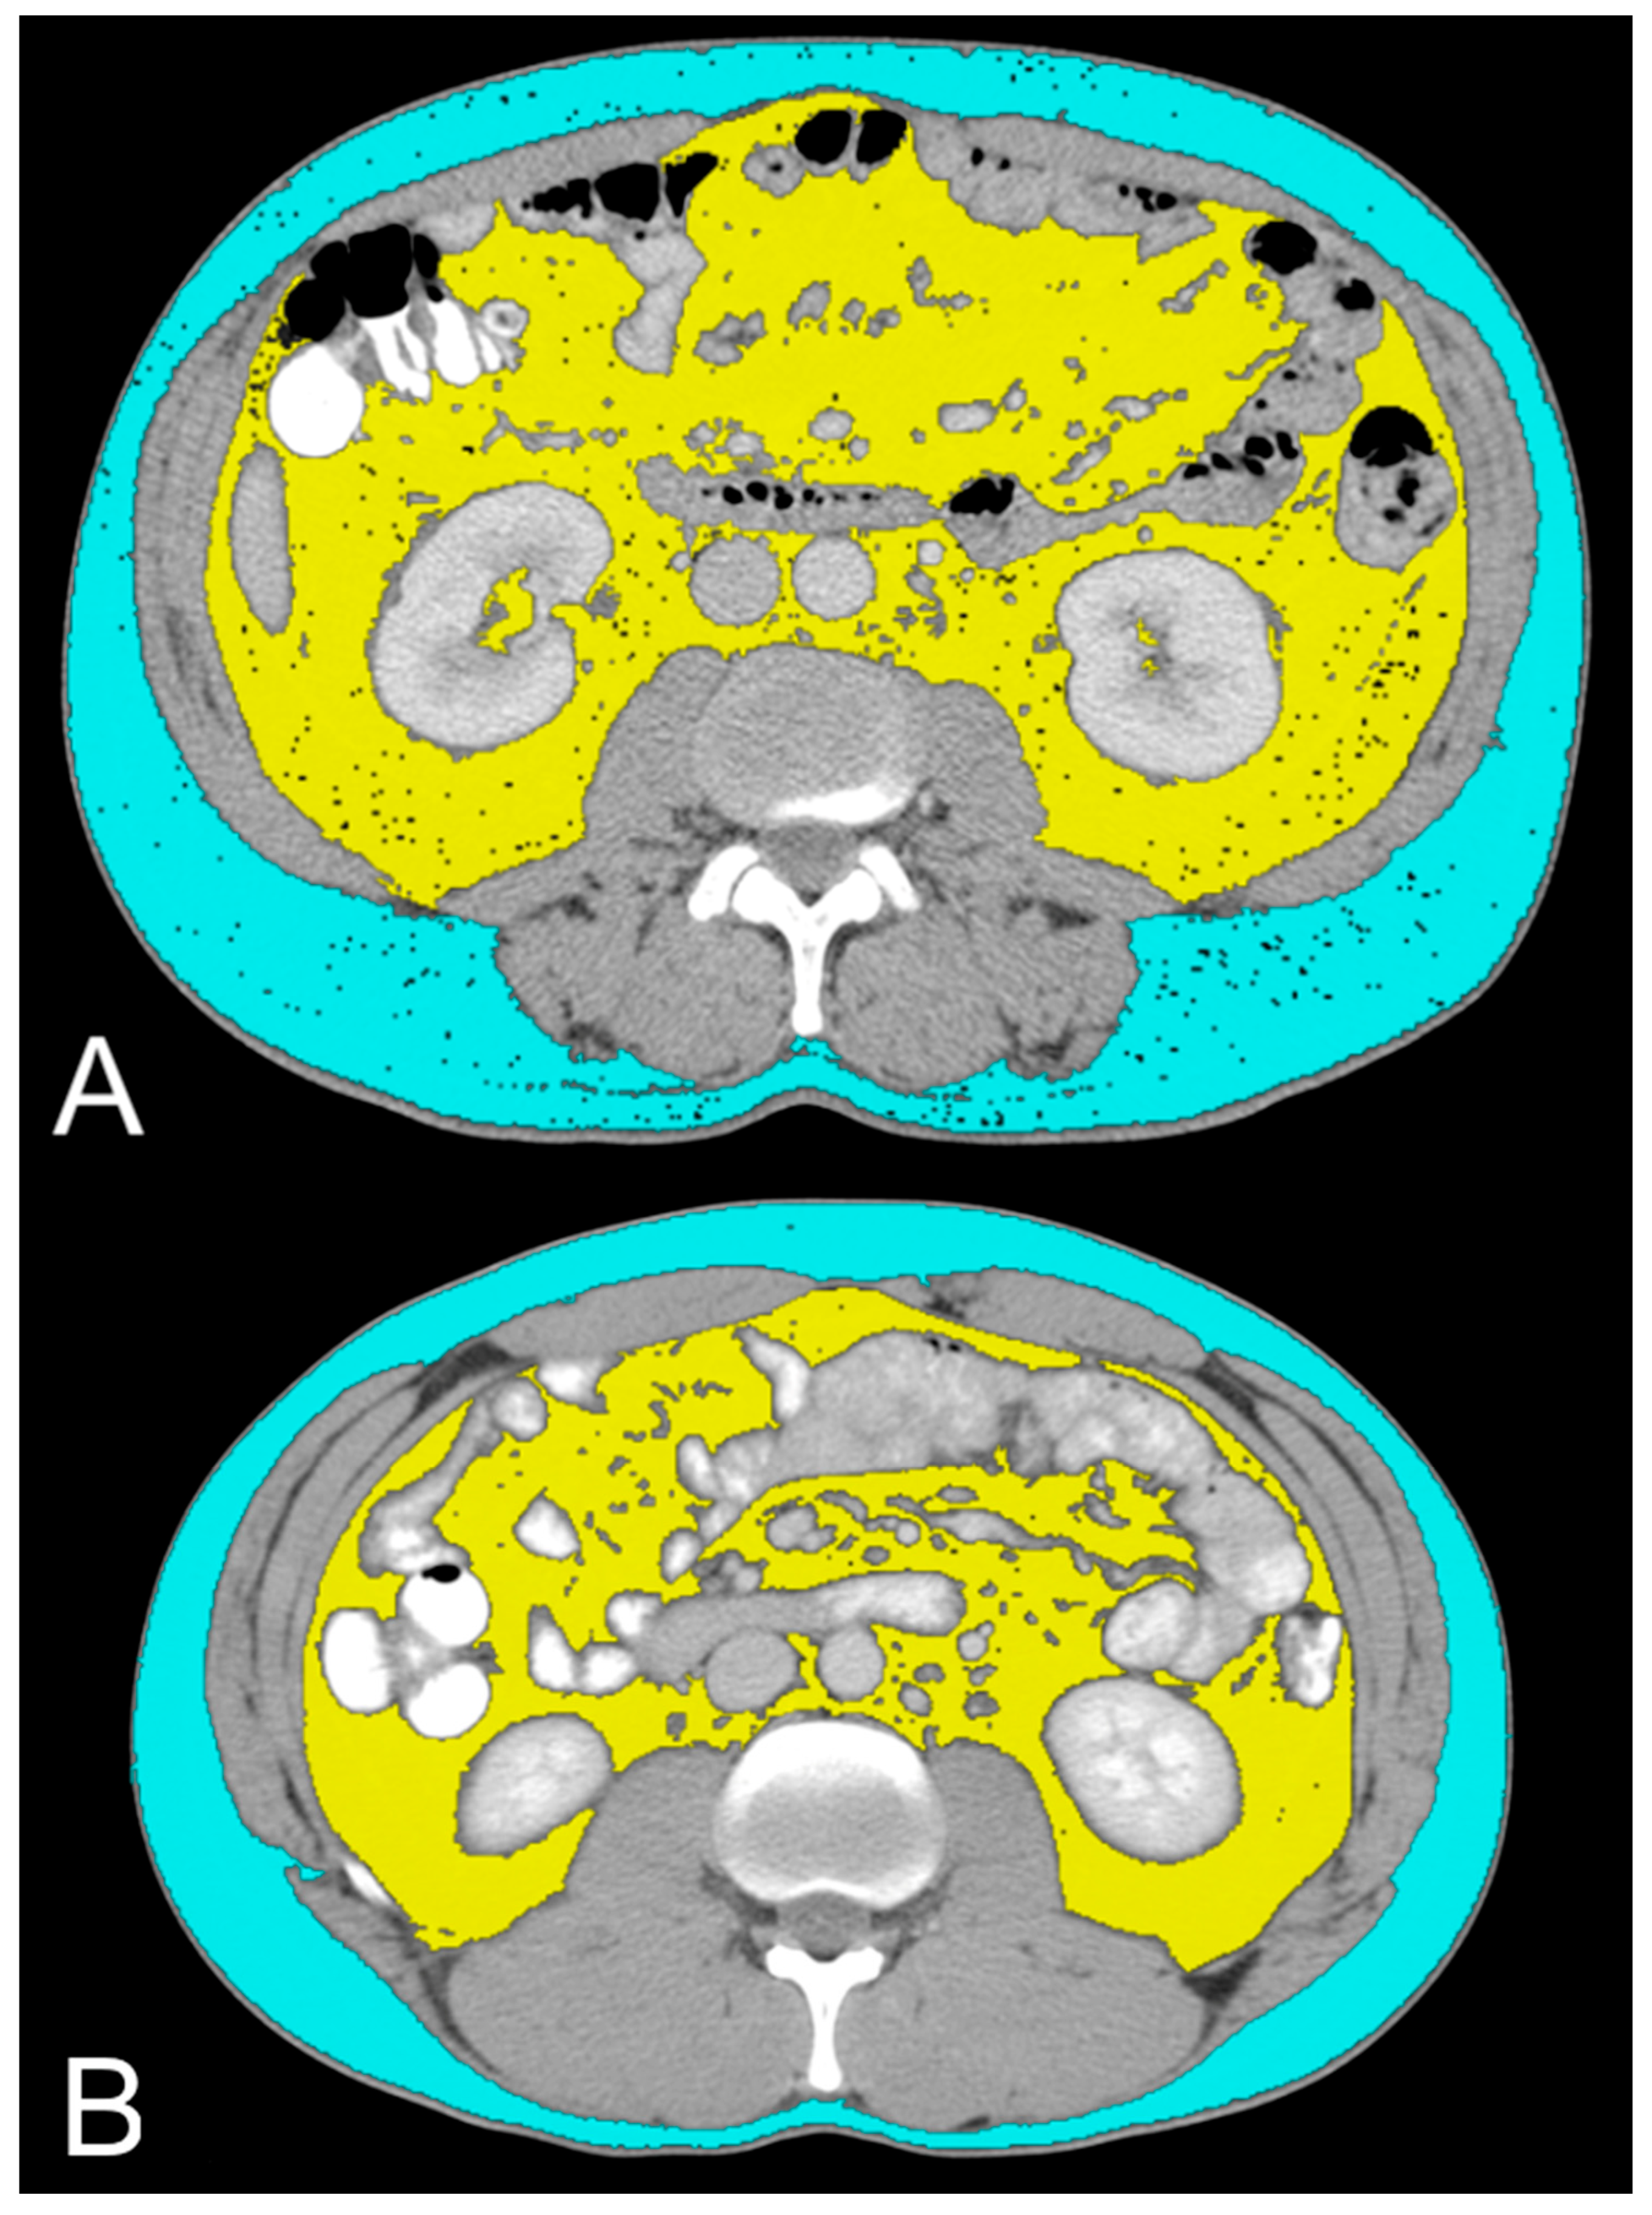

- Noumura, Y.; Kamishima, T.; Sutherland, K.; Nishimura, H. Visceral adipose tissue area measurement at a single level: Can it represent visceral adipose tissue volume? Br. J. Radiol. 2017, 90, 20170253. [Google Scholar] [CrossRef]

- Greco, F.; Quarta, L.G.; Grasso, R.F.; Beomonte Zobel, B.; Mallio, C.A. Increased visceral adipose tissue in clear cell renal cell carcinoma with and without peritumoral collateral vessels. Br. J. Radiol. 2020, 93, 20200334. [Google Scholar] [CrossRef] [PubMed]